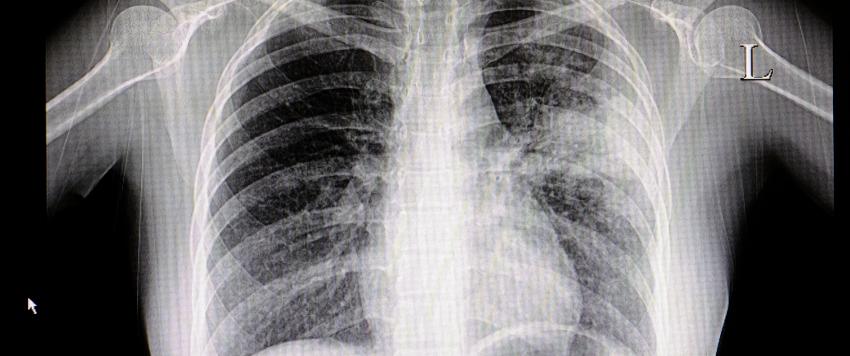

تليف الرئة من الأمراض الخطيرة التي قد تصيب الإنسان لما له من مضاعفات خطيرة، ويحدث نتيجة هذا المرض نقص فى كمية الأكسجين المتجهة إلى كافة أجهزة الجسم مما يسبب العديد